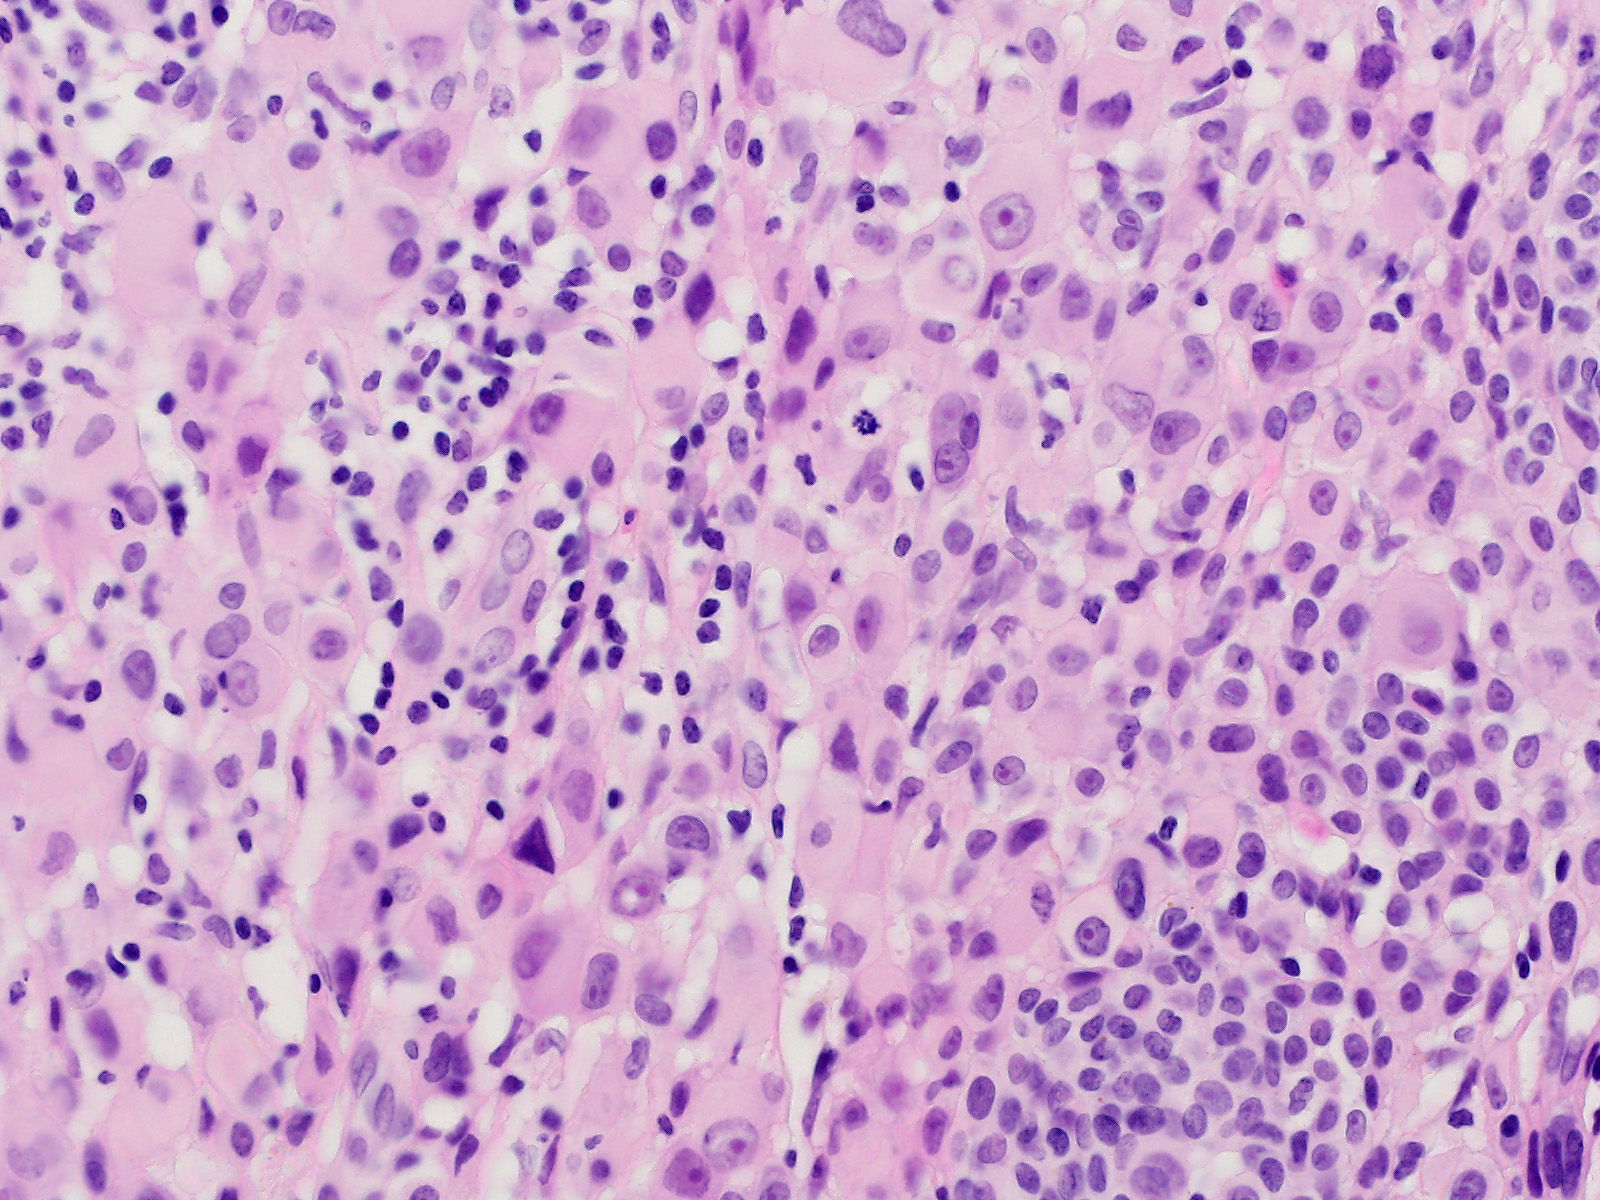

Biphänotypischer Naevus mit einer kleinzelligen gewöhnlichen Naevuskomponente und einer atypischen epitheloidzelligen Komponente. Die atypische Epitheloidzellkomponente besteht aus grossen Melanozyten mit reichlich glasigem Zytoplasma, klar definierten Zellgrenzen und grossen, vesikulären, leicht pleomorphen Zellkernen mit prominenten eosinophilen Nukleolen. An einigen Stellen sind tumorinfiltrierente Lymphozyten erkennbar sowie eine Mitosefigur.

Die grossen epitheloiden Zellproliferate zeigen einen Verlust der BAP1 Expression im Zellkern. Die Zellkerne des gewöhnlichen Naevusanteils sind positiv. Beide Komponenten sind immunhistochemisch positiv für die BRAF V600E Mutation.

In Wiesner's nevu, classic features of Spitz nevus, such as Kamino bodies, spindle-shaped melanocytes, epidermal hyperplasia and clefting around junctional melanocytic nests, are absent. These tumors may be sporadic or appear multiple in patients with an autosomal dominant syndrome caused by germline mutations in BAP1. Both sporadic and Wiesner nevi in the familial syndrome show BRAF V600E mutation and loss of nuclear staining for BAP1. If a BAP1 mutation is confirmed in a tumour, the patient's treating physician should be informed of the possibility of a BAP1 germline mutation, so they can consider whether genetic counselling and further testing of the patient and investigation of their family is appropriate. Wiesner's nevi may present as a pure large epithelioid cell proliferation or as in this case as a combined lesion in association with a conventional nevus. Pathology. 2013 Feb;45(2):116-26. Tumours associated with BAP1 mutations. Murali et al. Am J Surg Pathol. 2013 Feb;37(2):193-9. Combined BRAF(V600E)-positive melanocytic lesions with large epithelioid cells lacking BAP1 expression and conventional nevomelanocytes. Busam et al.